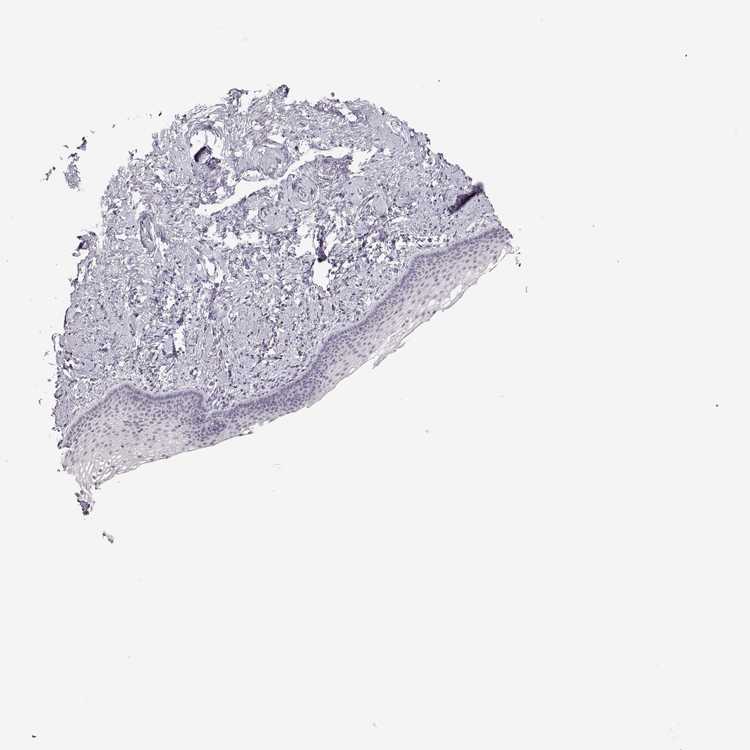

TISSUE PRIMARY DATA VAGINA Show tissue menu

VAGINA - Antibody stainingi

Antibody staining in the annotated cell types in the current human tissue is reported as not detected, low, medium, or high, based on conventional immunohistochemistry profiling in selected tissues. This score is based on the combination of the staining intensity and fraction of stained cells.

Each image is clickable and will lead to virtual microscopy that enables deeper exploration of all samples and also displays staining intensity scores, fraction scores and subcellular localization as well as patient and tissue information for each sample.

Antibody HPA049627

Squamous epithelial cells Not detected